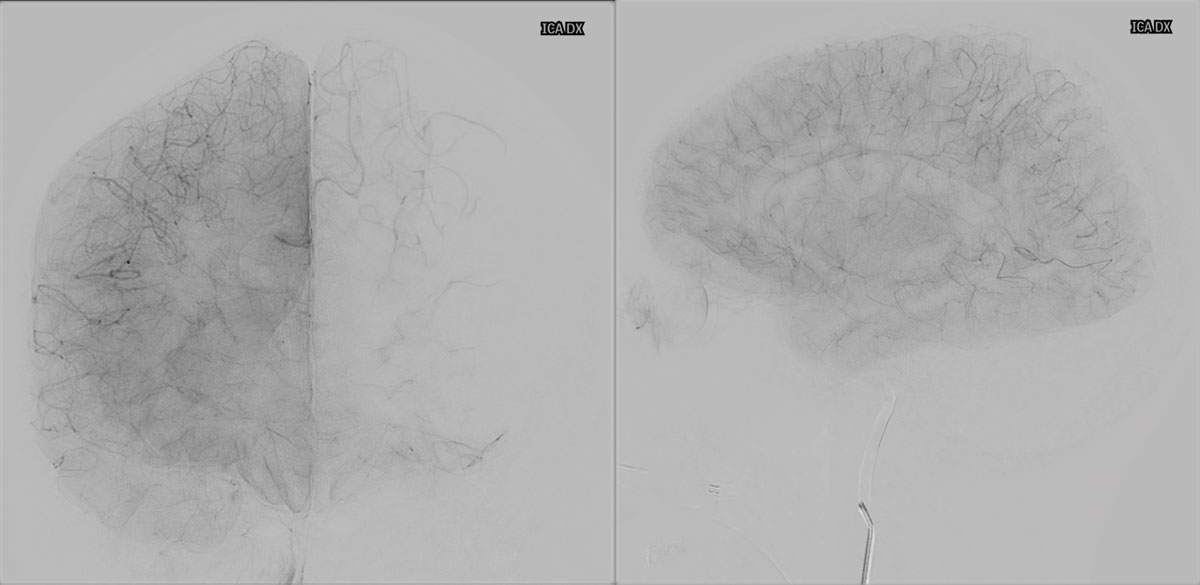

VASO-CT post

24h CT-scan

24h CTA and CTP

6 months DSA follow up